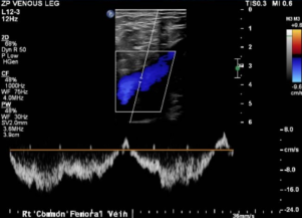

Doppler Venous Left Lower Extremity

Normal Doppler venous examination of the left lower extremity. There is no evidence of deep venous thrombosis.